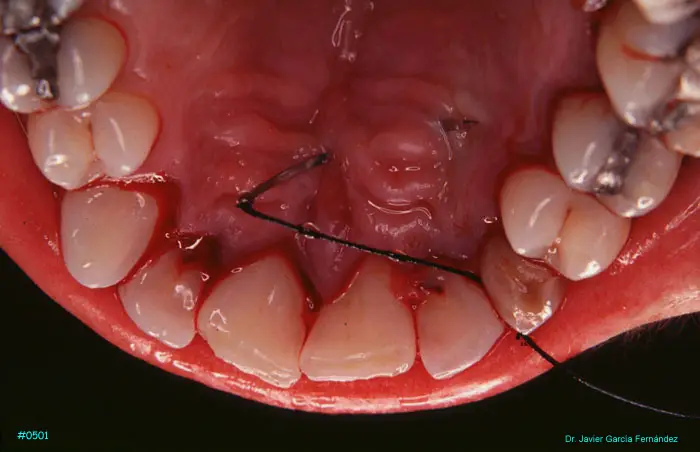

Atlas of Surgical Techniques in Periodontics. Chapter II. Atlas de Técnicas Quirúrgicas en Periodoncia